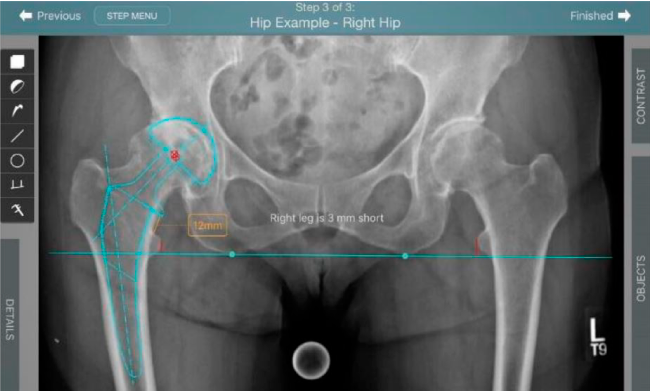

Planeación preoperatoria mediante la creación de plantillas digitales para reemplazo de cadera y análisis intraoperatorio

• Aumenta la precisión y reproducibilidad quirúrgica generando resultados predecibles.

• Datos procesables en tiempo real para la toma de decisiones.

• Mejora los resultados de los pacientes disminuyendo riesgos.

• Favorece la restauración biomecánica del offset femoral.

Beneficios de la planeación preoperatoria con Velys Hip Navigation ™

• Disponibilidad de plantillas digitales de cadera.

• Expediente histórico y personalizado, optimiza la planeación con el calendario de casos realizados en Velys TM y utiliza los íconos interactivos para una rápida revisión.

• Espacio colaborativo: puede compartir los casos entre cirujanos y sus equipos mediante la funcionalidad de intercambio de información.

• Anotaciones digitales y herramientas de análisis de longitud de pierna.

• Con tecnología ONETRIAL® que calcula automáticamente el cambio en la longitud de la pierna y el desplazamiento para todas las combinaciones de implantes en una tabla fácil de leer.